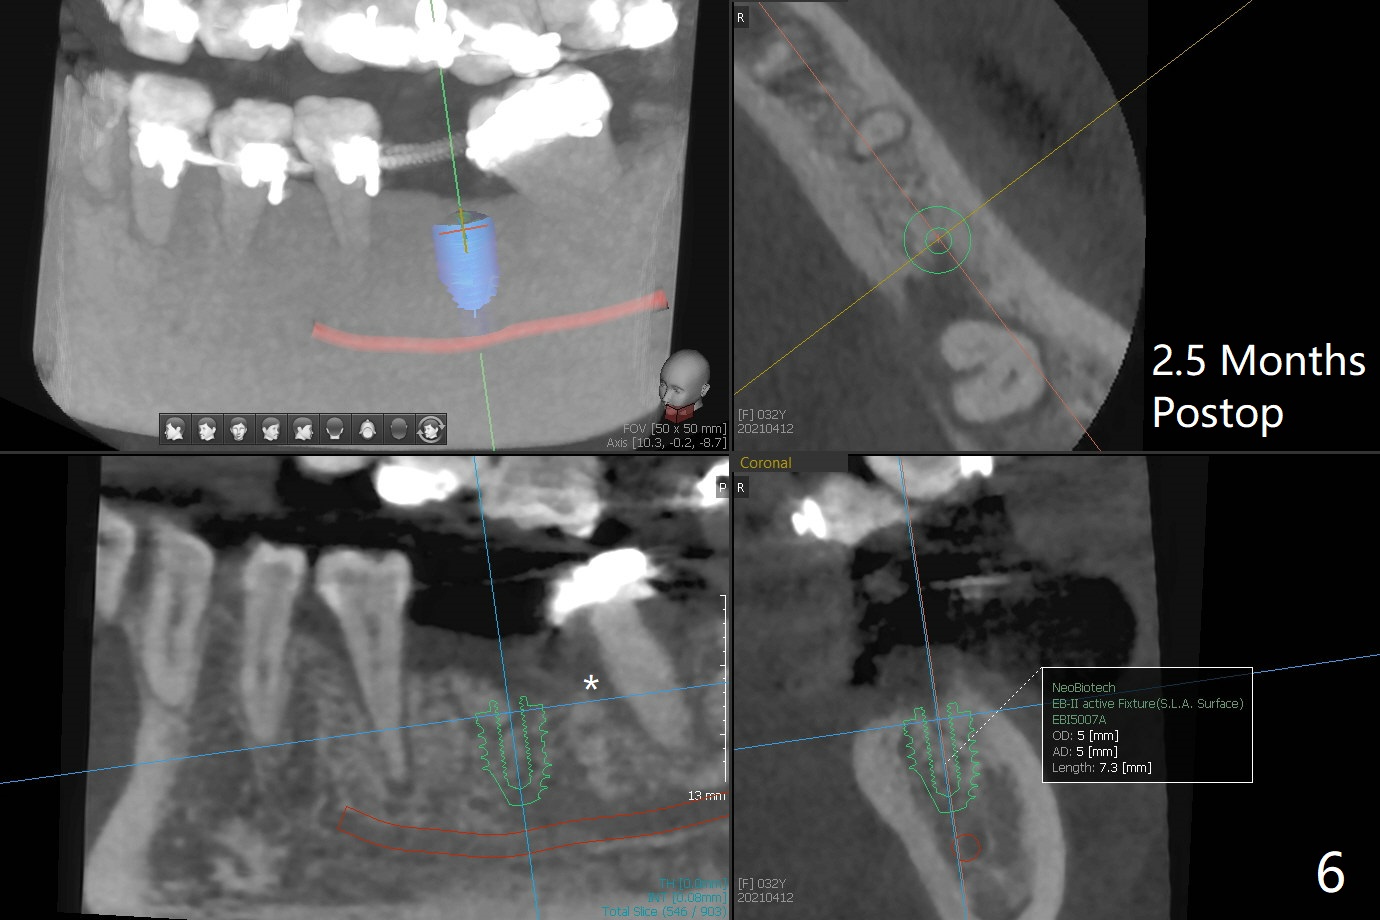

前几周介绍一个矫正砸锅病例,微型植体植入左上6(for intrusion,矫正压低)颊侧远中没有骨质区域,造成局部骨质缺损(图一:>)。颊侧,腭侧牙龈沟切口,翻瓣,清创后,植入粘性骨粉(图二:*,也在颊侧,腭侧植骨),覆盖PRF膜,使用4-0 Monoglyc缝线缝合。对于左下6缺失,原先病人(31岁女)要求前移7,8,初步矫正(2个月内)引起7松动(图三),经过讨论,病人同意拔除8,然后竖直7。拔出后,放置半块胶原塞(控制出血,图四:C),然后植骨(*),最后放置另外半块胶原塞(C),4-0 PGA缝合。术后一个月腭侧放置power chain压低磨牙(图五)。术后2.5个月缺牙间隙大于前磨牙,可以种植,同时7近中植骨(图六:*(粘性骨粉))。整合后利用6作为抛锚继续做7竖直。